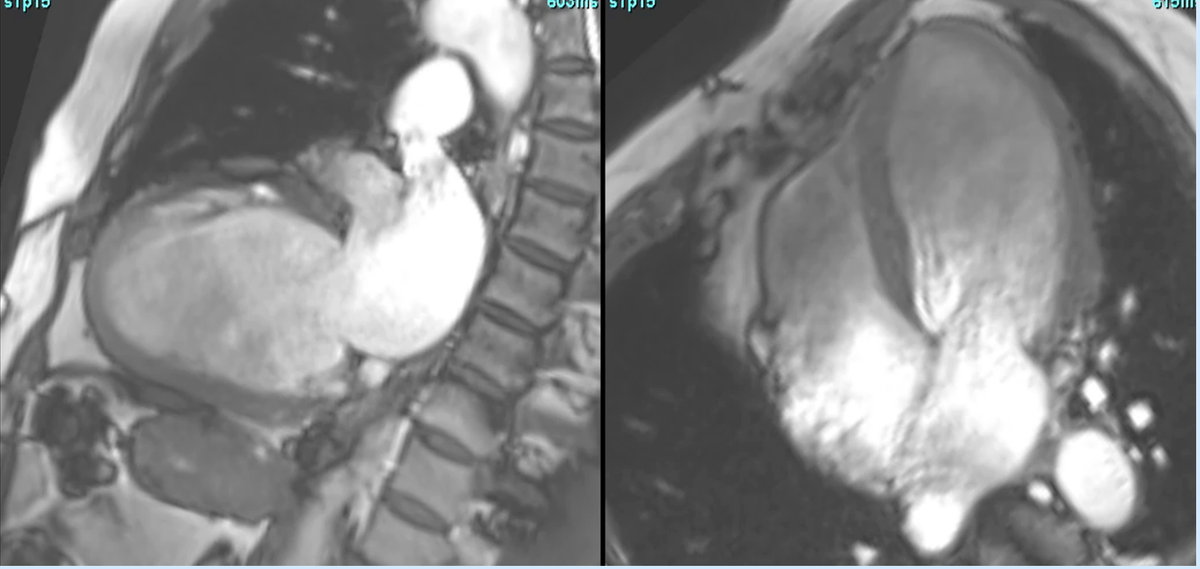

CMR in valvular HD